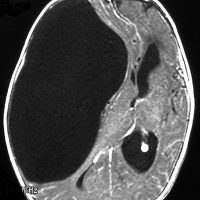

9歳男児の松果体奇形腫です。生検術と第3脳室開窓術を受けましたが,摘出術のリスクが高すぎるということで化学療法を6コース。2年間経過観察されましたが,腫瘍が増大しました。私のところへ来た時には,前後径73mmありました。

左からT2, swan, T1です。これが 類皮のう胞 dermoid cyst ということがわかります。類皮のう胞単独,あるいは成熟奇形腫の大部分としての類表皮のう胞は,かなり頻度の高いものです。松果体腫瘍で奇形腫を疑ったらまず,類皮のう胞の混在を疑います。それがあれば,かなりの確率で成熟奇形腫 mature teratomaです。

類皮のう胞は内部がほとんど皮脂,ケラチン,汗,毛髪なので,簡単に砕けるし,掻き出し吸い取ることができます。松果体成熟奇形腫の中では最も戦いやすい相手と言えるでしょう。再発しないようにするには,周囲ののう胞壁(真の腫瘍細胞)を完全摘出するしかありません。放射線も化学療法も何も効かないし,のこせば必ず再発します。

右迂回槽にちょっとdebrisは残っていますが完全摘出できました。病理は他の成分を少し混じる成熟奇形腫です。術後3年間再発はありませんし,学校へ通って体育もできています。

この手術はもちろん簡単ではありません,でもほとんどが類皮のう胞であるということがわかったので踏み込めたのです。